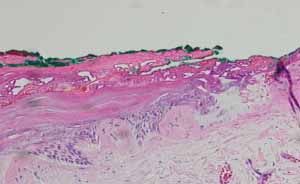

日々の治療や通院により、口腔内の異変を発見することもあります。よりしっかりとした判断が必要な場合などは、口腔内の生検(組織検査)が必要です。生検は、外科的に切開して組織を採取することで行われます。

生検は、病変の代表的な部位から採取すべきです。病変の大きさや範囲のために切除が不可能な場合は、各反応パターンの代表的な部位から切開生検を行う必要があります。

切開生検では、直径が異なる(通常 3~8 mm)パンチ生検(円筒形のナイフ)を使用することが有効である場合があります。正確な診断を確実に得るためには、病変内の代表的な領域およびすべての反応パターンからサンプルを採取することが重要です。そのため、可能な限り大きな直径(少なくとも 4 mm)のパンチ生検器具を選択する必要があります。